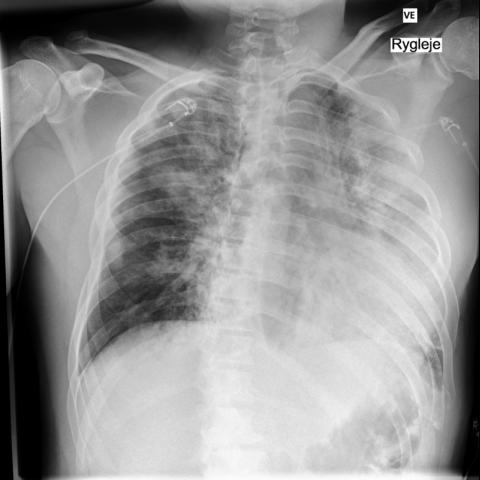

第 4 天复查,胸部 X 光显示肺部浸润明显减轻,与患者的临床恢复相对应。

经过 6 天的住院,患者恢复出院。

所有影像检查有效地记录了患者从严重肺窘迫到逐渐恢复的过程。